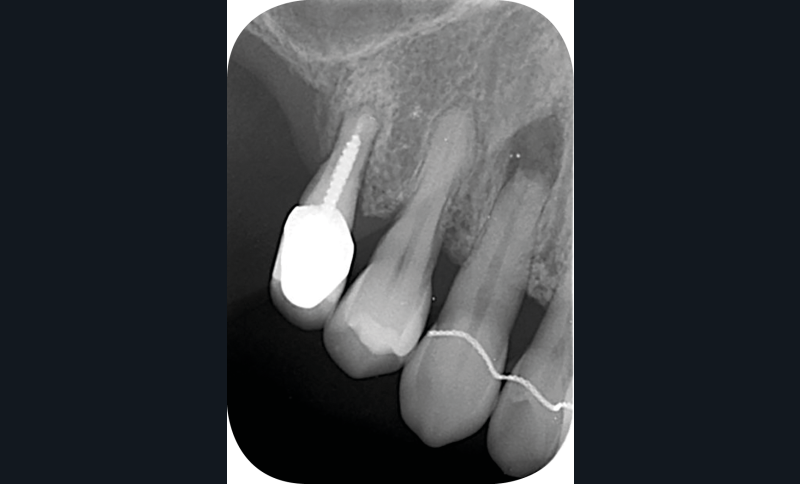

– la nécrose, qui va donner une coloration plutôt brune [3] (fig. 1, 2) ;

– le trauma, qui va donner une couleur plutôt rouge [4] (fig. 3) ;